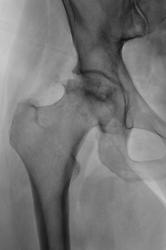

Тазобедренный через год.

В своё время подмеченное Вами, не было достойно оценено, хотя "мнения были", и через год мы "поимели" следующее....

Снимки добавлены.

Ну вот, он и есть асептический некроз головки бедра.

Год назад была 1 стадия, сейчас импрессия,фрагментация. Протез нужен, дальше будет только хуже,т.к. вовлечение вертлужной впадины неизбежно.

Первые снимки - вторая стадия, последние снимки - пятая. О протезировании задуматься уже даже поздно. Еще 0.5-1 год, и будет трудоемко ставить протез.... Похоже, дама вполне терпеливая.

P.S. Евгений опередил... я по 5-стадийной классификации (Рейнберга)))